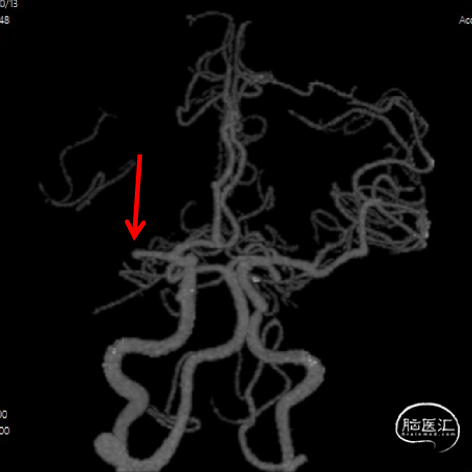

CTA

DSA

1、急性脑梗死。2、左侧大脑中动脉M1段闭塞。

ICAS合并血栓?

夹层合并血栓?

栓塞?